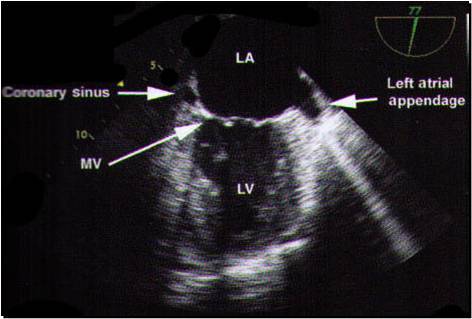

This is looking down to mitral valve

I think this might be the most important picture for TEE

Here’s an easy 4 chamber view